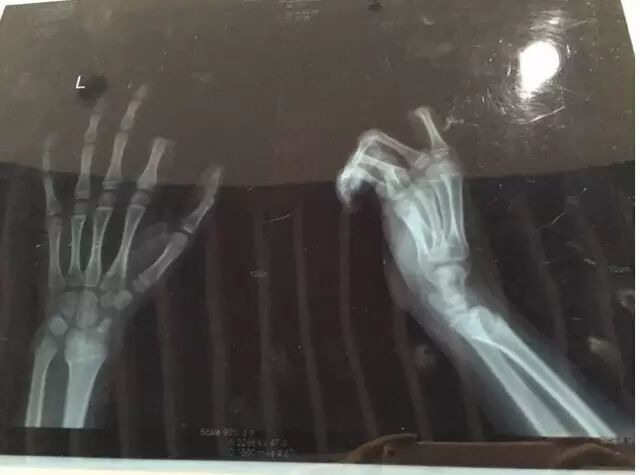

拿起菜刀,朝左手切去,兩個(gè)指節(jié)當(dāng)場(chǎng)就掉了下來(lái)

據(jù)了解,這個(gè)孩子小朋(化名)今年才11歲,出事后,家長(zhǎng)立即帶著他和切下的手指來(lái)到醫(yī)院。

不一會(huì)兒,飯做好了,聽(tīng)見(jiàn)這段對(duì)話(huà)的鄒某,已經(jīng)對(duì)小朋一直玩游戲的狀態(tài)有些不滿(mǎn),便忍不住對(duì)小朋訓(xùn)斥了幾句。當(dāng)時(shí),小朋手里正拿著叉子在叉土豆泥吃,聽(tīng)了爸爸訓(xùn)斥的話(huà)后,立馬就炸毛了,放下手中的叉子,轉(zhuǎn)身就拿起了身后矮桌上的菜刀,朝著自己的左手切下去,當(dāng)場(chǎng),食指的兩個(gè)指節(jié)就掉了下來(lái)。

小朋的父母都沒(méi)想到孩子會(huì)做出如此舉動(dòng),看到手指掉下來(lái)了,都愣住了。隨后,二人又立刻反應(yīng)過(guò)來(lái),將斷肢用紙包好,放進(jìn)口袋,帶著小朋便趕到了醫(yī)院。

手術(shù)歷經(jīng)3個(gè)多小時(shí)。醫(yī)生表示,若能順利度過(guò)了一個(gè)星期的危險(xiǎn)期,接上去的手指便能成活。